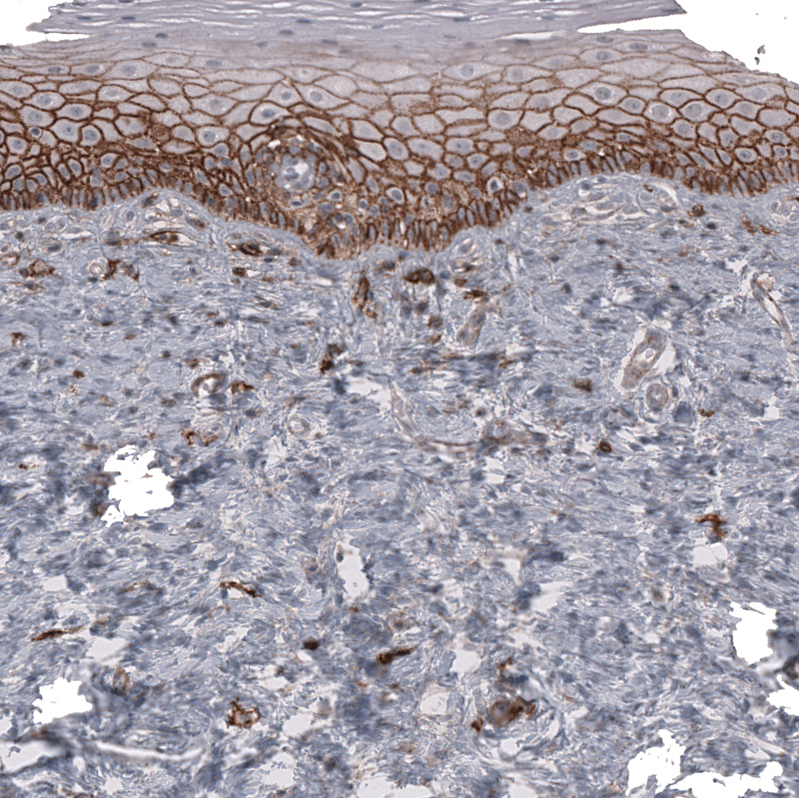

Immunohistochemistry analysis in human cervix, uterine and skeletal muscle tissues using AMAb91848 antibody. Corresponding CD44 RNA-seq data are presented for the same tissues.